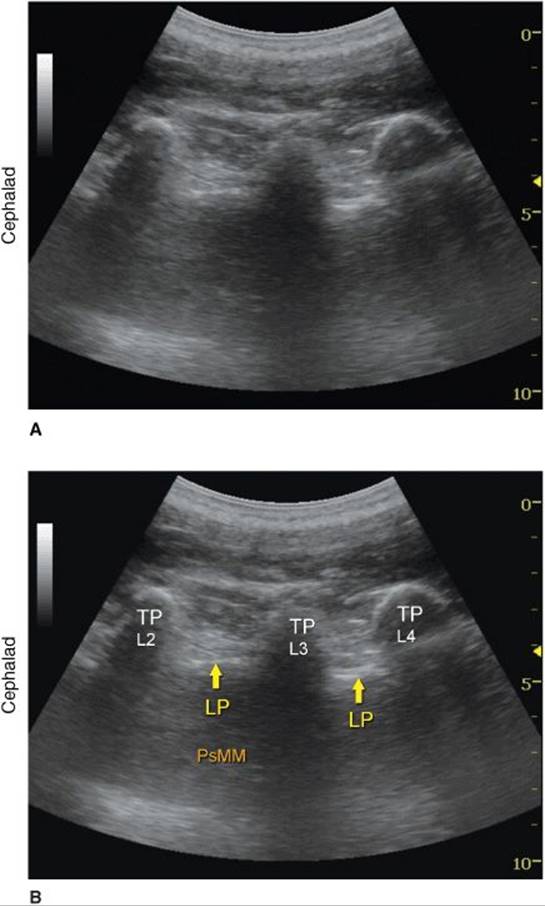

Regardless of the technique, the operator first should identify the transverse processes on a longitudinal sonogram (Figure 46-1). One technique is to first identify the flat surface of the sacrum and then scan proximally until the intervertebral space between L5 and S1 is recognized as an interruption of the sacral line continuity. Once the operator identifies the transverse process of L5, the transverse process of the other lumbar vertebrae are easily identified by a dynamic cephalad scan in ascending order. The acoustic shadow of the transverse process has a characteristic appearance, often referred to as a “trident sign” (Figure 46-2A). Once the transverse processes are recognized, the psoas muscle is imaged through the acoustic window of the transverse processes. The psoas muscle appears as a combination of longitudinal hyperechoic striations within a typical hypoechoic muscle appearance just deep to the transverse processes (Figure 46-2B). Although some of the hyperechoic striations may appear particularly intense and mislead the operator to interpret them as roots of lumbar plexus, the identification of the roots in a longitudinal scan is not reliable without nerve stimulation. This unreliability is partly due to the fact that intramuscular connective tissue (e.g., septa, tendons) within the psoas muscle are thick and may be indistinguishable from the nerve roots at such a deep location. As the transducer is moved progressively cephalad, the lower pole of the kidney often comes into view as low as L2-L4 in some patients (Figure 46-3A and B).

FIGURE 46-2. (A) Ultrasound anatomy of the lumbar paravertebral space demonstrating transverse processes at a depth of approximately 3 cm. Lower frequency, curved transducer is used optimize imaging at the deep location and obtain a greater angular view, respectively. (B) Labeled ultrasound anatomy of the lumbar paravertebral space with structures labeled. TP, transverse process; LP, lumbar plexus roots (most likely); PsMM, psoas major muscle.